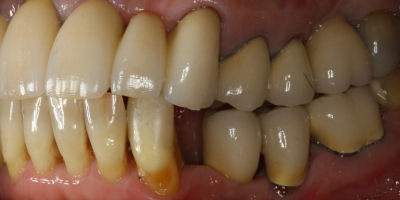

Before/After